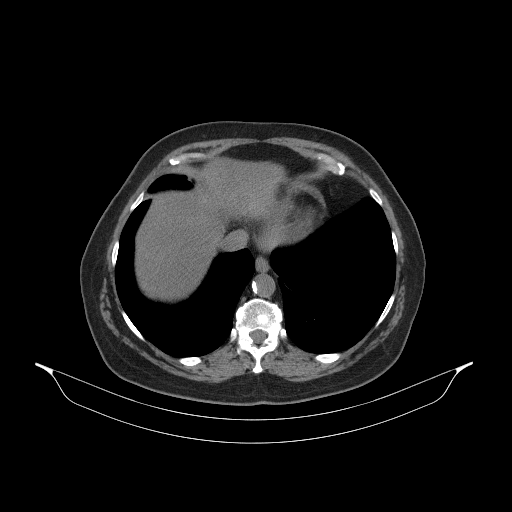

Generated VENOUS CT scan (A→B translation)

No window - Raw intensity values

Lung window (WL -600, WW 1500 β†’ Low βˆ’1350, High +150)

Mediastinum window (WL 40, WW 400 β†’ Low βˆ’160, High +240)